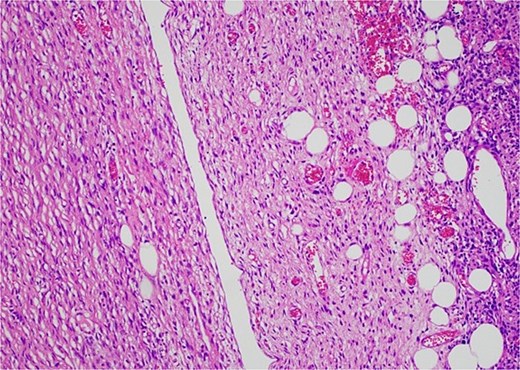

Histology revealed a multilobulated spindle cell lesion, with low- and high-grade areas, with an abrupt transition between these areas. There was an adjacent focus of adipose tissue with rare cytologic atypia suggestive of possible WDL, which indicated that the tumor mass may represent DDL. However, there was a single focus of lipoblasts identified, bringing up the differential of pleomorphic liposarcoma. Therefore, in situ hybridisation was performed and showed MDM2 amplification, which confirmed the diagnosis of DDL, with likely homologous lipoblastic morphology. The tumour was excised with clear margins (Figs 3–8).

Low-grade component with spindle cells with tapered nuclei and indistinct cytoplasm that merges into a delicate collagenous stroma.